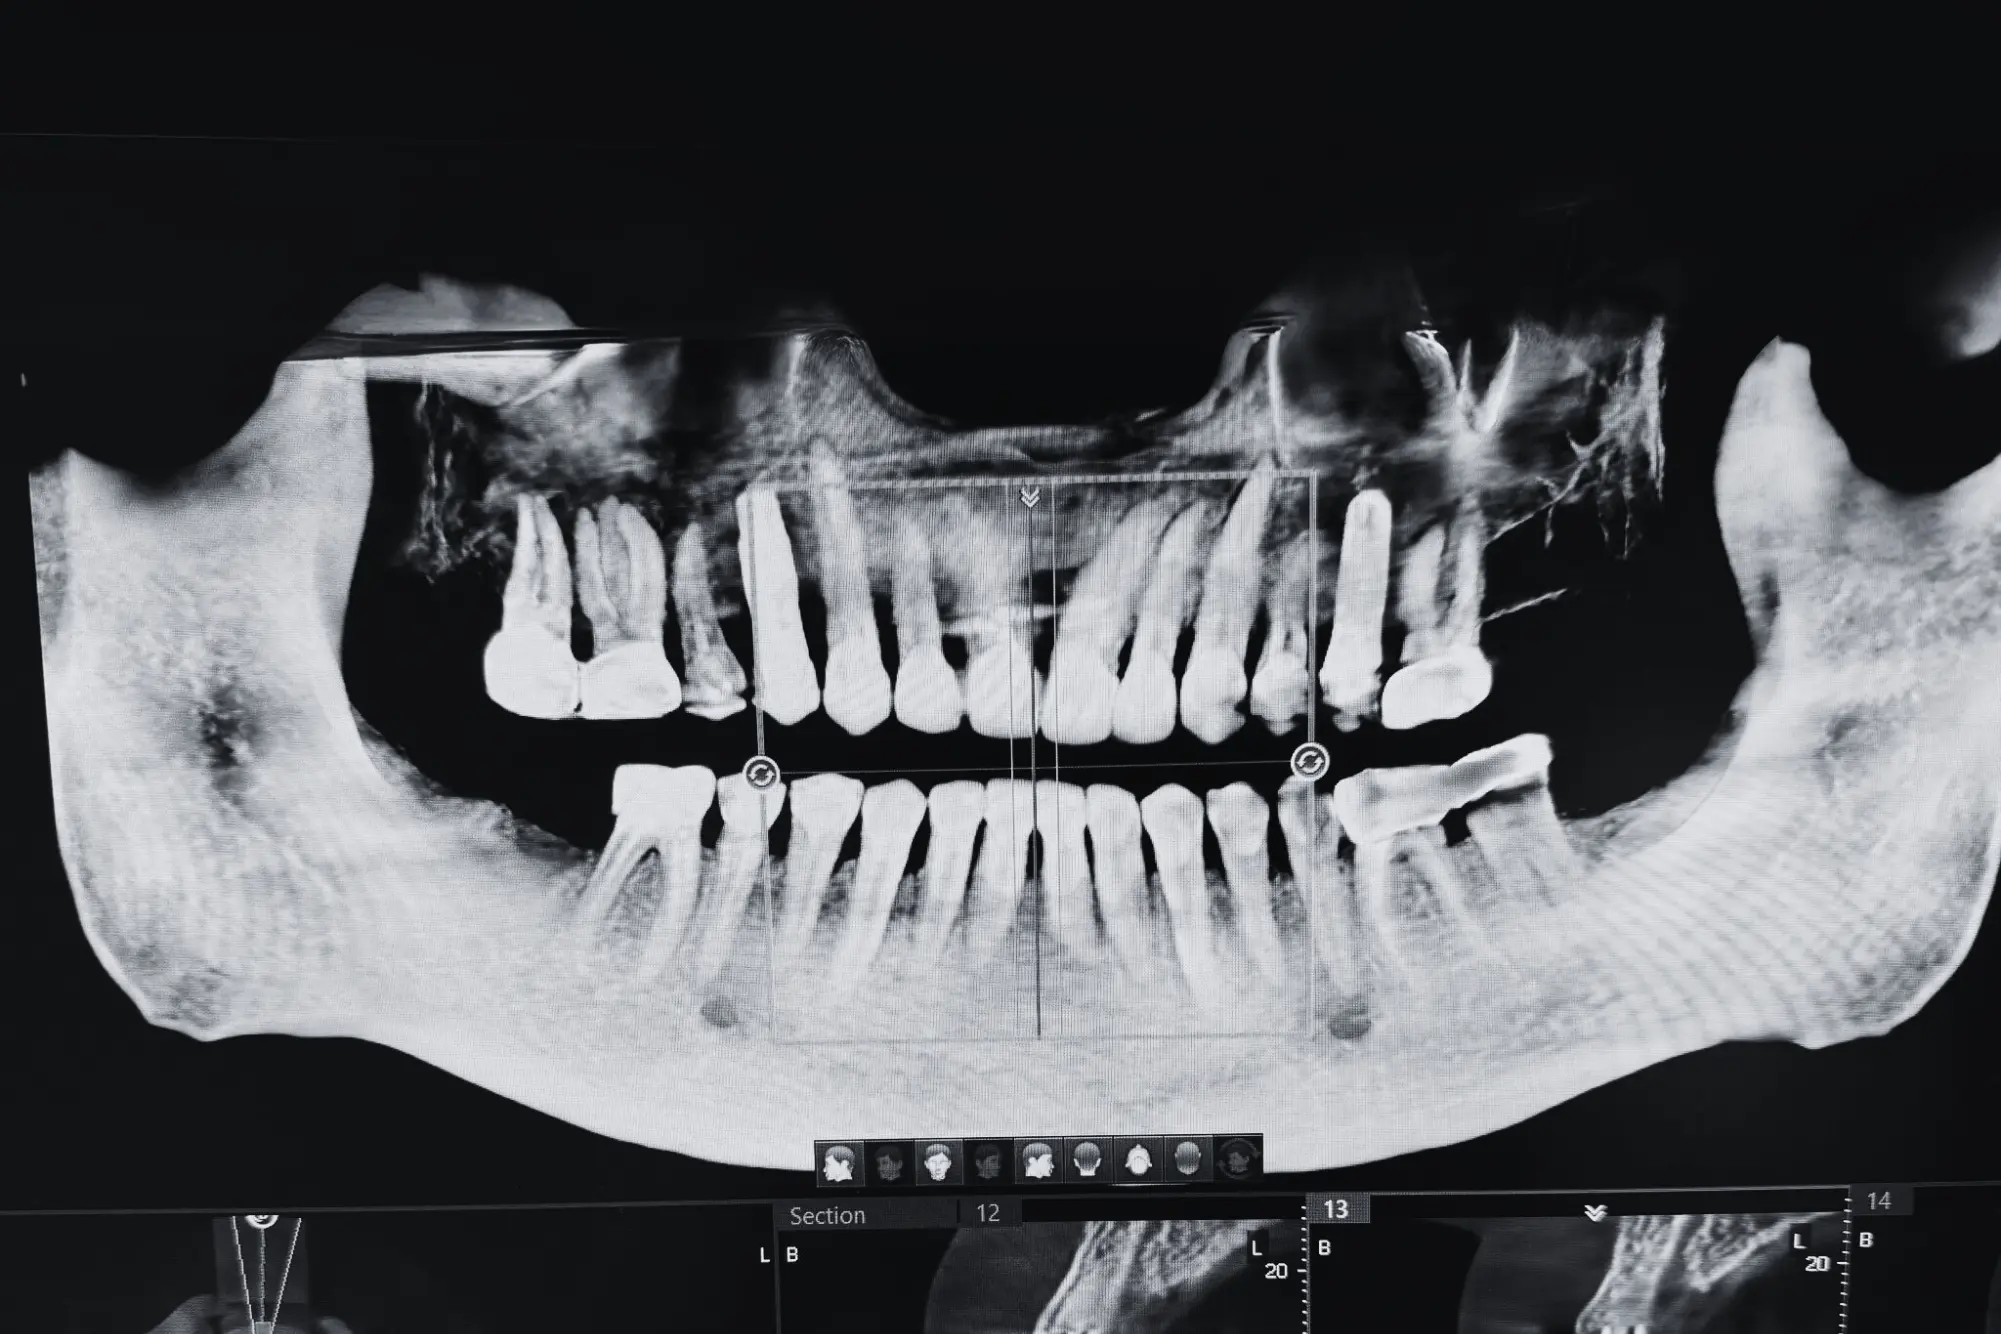

Dental implants are artificial roots used to replace missing teeth. Their biocompatible surfaces stimulate bone fusion, ensuring they function like natural teeth when fixed to crowns or bridges. With millions used globally each year, their popularity is rising due to their high success rate.

- 3D Planning for safe and predictable surgery (Nobelguide).

- 3D pre-planning ensure the intended prosthetic outcome.